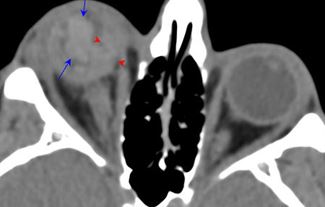

Facial and Scalp Soft Tissues and Airway

There is localized edema, hematoma or abscess within in the facial or scalp soft tissues, SMAS, infratemporal fossa, masticator space or oral cavity.

There is evidence of gas or a foreign body at a possible fracture site, indicative of an open or penetrating injury.

There is soft tissue swelling suggesting injury to the parotid or submandibular glands.

Orbits and Orbital Zygomatic Complex

There is evidence of a subperiosteal hematoma along the medial or lateral wall, roof or floor of the orbit.

The circumferential extraconal and the intraconal orbital fat are infiltrated.

There is evidence of herniated intra-orbital fat.